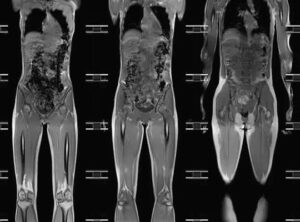

Магнитно-резонансная томография всего организма

МРТ всего тела позволяет выявить скрытые патологические процессы на ранней стадии развития. Это тест, который оценивает состояние органов и тканей организма, распознает патологию и определяет степень развития болезненного процесса. Магнитно-резонансная томография дает возможность получить подробную информацию о состоянии пациента без боли, ущерба для здоровья и потери времени. Зачем проводят МРТ всего тела Есть много причин, …